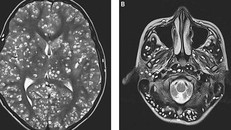

Nhân viên y tế tiến hành lấy mẫu xét nghiệm ở trẻ